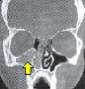

Tac cranio normale

Sinusite mascellare polipi nasali a destra